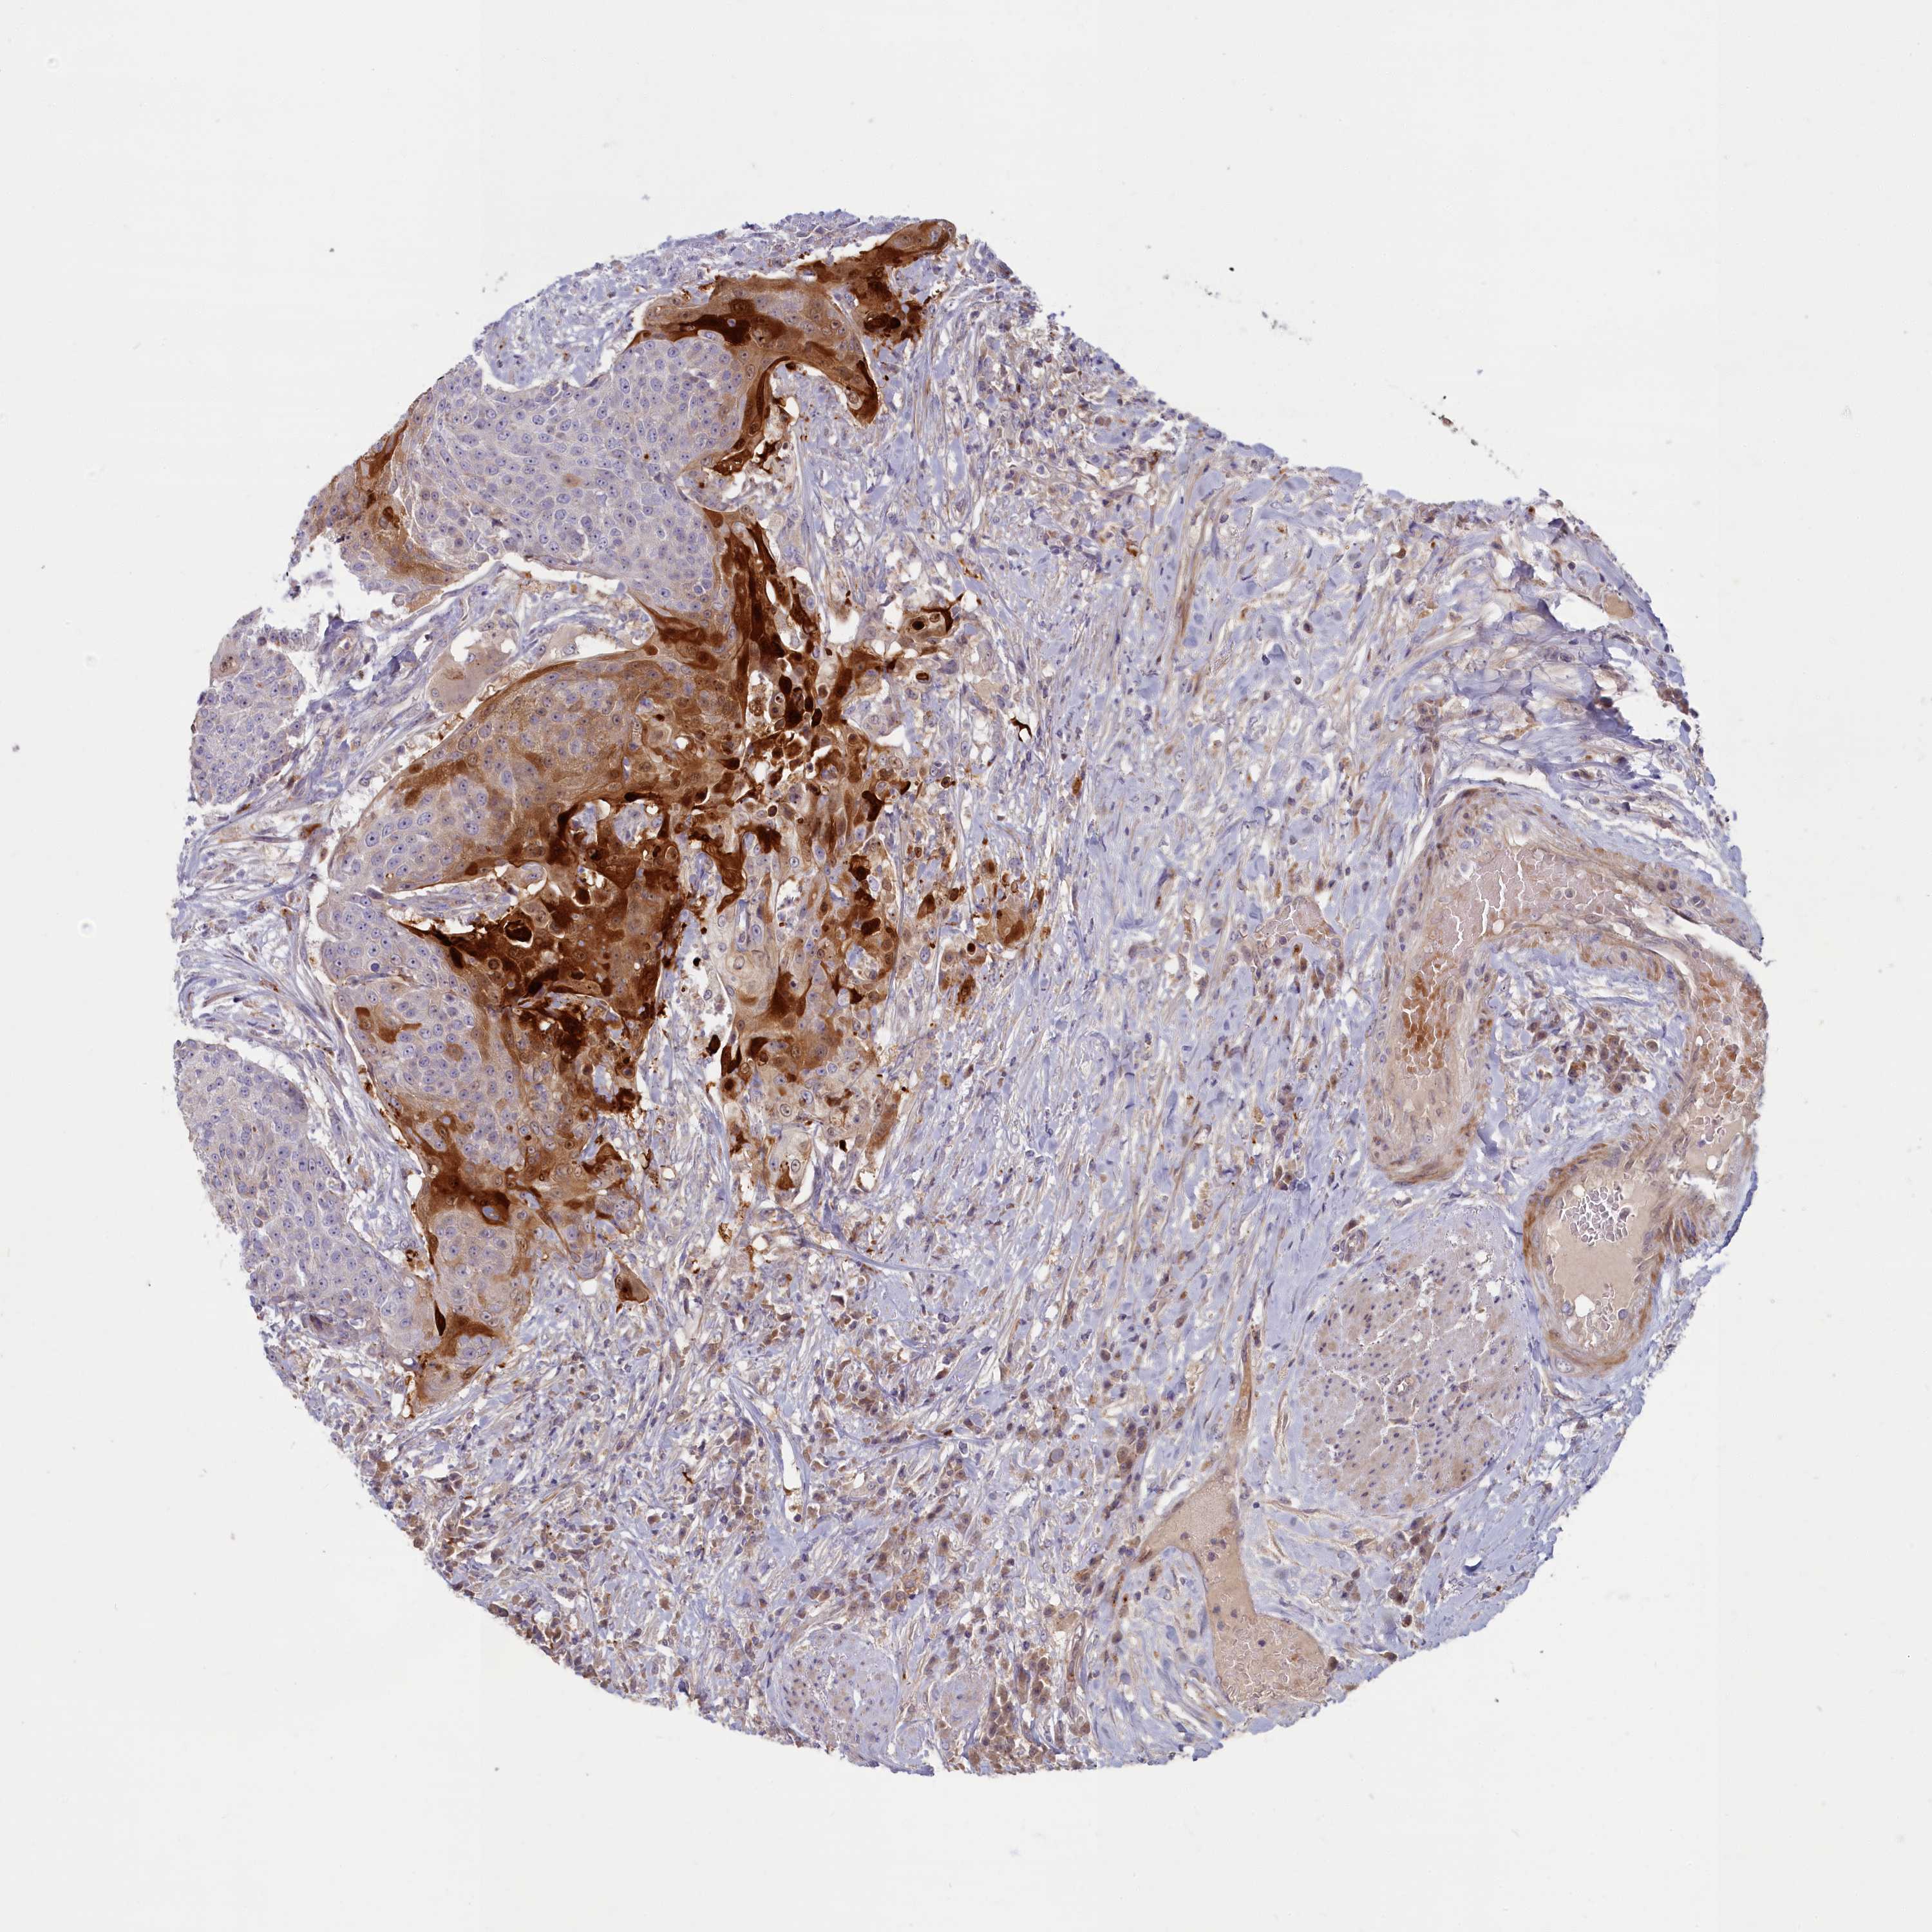

UROTHELIAL CANCER - Protein expressioni

A mouse-over function shows sample information and annotation data. Click on an image to view it in a full screen mode. Samples can be filtered based on level of antibody staining by selecting one or several of the following categories: high, medium, low and not detected. The assay and annotation is described here.

Note that samples used for immunohistochemistry by the Human Protein Atlas do not correspond to samples in the TCGA dataset.

Antibody stainingi

Antibody staining in the annotated cell types in the current human tissue is reported as not detected, low, medium, or high, based on conventional immunohistochemistry profiling in selected tissues. This score is based on the combination of the staining intensity and fraction of stained cells.

Each image is clickable and will lead to virtual microscopy that enables deeper exploration of all samples and also displays staining intensity scores, fraction scores and subcellular localization as well as patient and tissue information for each sample.

Antibody HPA041971

Staining

High

Medium

Low

Not detected

Intensity

Strong

Moderate

Weak

Negative

Quantity

>75%

75%-25%

<25%

None

Location

Nuclear

Cytoplasmic/membranous

Cytoplasmic/membranous,nuclear

Urothelial carcinoma, High grade

Urothelial carcinoma, Low grade